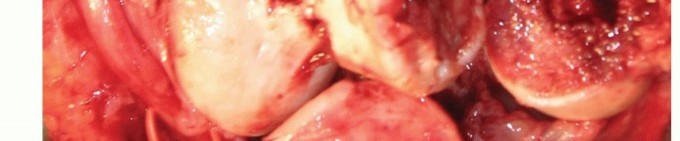

TECH FIG 3 • (continued) D. Comminuted distal humeral fracture in an osteoporotic elderly woman, with CT imaging confirming significant articular comminution. This is the view through the triceps split.

TECH FIG 4 • A. The humeral component entry point, the apex of the olecranon fossa, is identified, and humeral canal preparation is commenced by opening the canal with a bone nibbler or burr. (continued)

TECH FIG 4 • (continued) B. The posterior flat surface of the humeral shaft is identified and the component is aligned. C,D. Ulnar canal preparation is commenced by opening the canal at the base of the coronoid process with a drill or burr. E. The trajectory of the ulnar component (black ring) is prepared by rasping the entry track posteriorly into the ulna with a rasp or bone nibbler (gray crescent). F,G. The tip of the coronoid should be resected sufficiently to prevent abutment on the humeral flange during full flexion. Also shown are the resections of the olecranon and the entry point for the ulnar stem insertion. H. The partially resected radial head is used as a bone graft for incorporation behind the humeral flange.